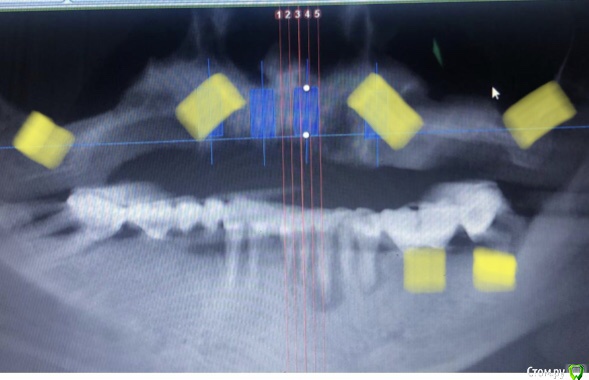

Nazim_NV86 Опубликовано 4 июля, 2020 Поделиться Опубликовано 4 июля, 2020 (изменено) Как расположить такой винт, чтобы не соприкасался с имплантом? Таблетку под углом к импоанту?1.Типа того2.У вас ФИО пациента видно. Желательно обрезать, то что выкладываете в сеть.3.Скачайте с оф сайта планмеки нормальную бесплатную версию. Там уже 6-я версия с мая этого года. И главное что ваш нарисованный план будет сохраняться. Изменено 4 июля, 2020 пользователем Nazim_NV86 2 Ссылка на комментарий

Александр07 Опубликовано 8 июля, 2020 Автор Поделиться Опубликовано 8 июля, 2020 1.Типа того2.У вас ФИО пациента видно. Желательно обрезать, то что выкладываете в сеть.3.Скачайте с оф сайта планмеки нормальную бесплатную версию. Там уже 6-я версия с мая этого года. И главное что ваш нарисованный план будет сохраняться. Спасибо Здесь больше похоже на миниблок) Ссылка на комментарий

Nazim_NV86 Опубликовано 8 июля, 2020 Поделиться Опубликовано 8 июля, 2020 СпасибоЗдесь больше похоже на миниблок)Это бета-версия. Ссылка на комментарий